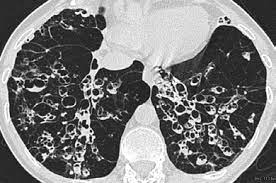

Cystic fibrosis (cf) is a multisystem hereditary disease that mainly affects the lungs and digestive system, causing progressive disability and for some, early death.

Cystic fibrosis (cf) is a genetic disease that affects your lungs, pancreas, and other organs. Cystic fibrosis is an inherited disease of the exocrine glands affecting primarily the gastrointestinal and respiratory systems. Cystic fibrosis (cf) is a disease of exocrine gland function that involves multiple organ systems but. Cystic fibrosis (cf) is a multisystem hereditary disease that mainly affects the lungs and digestive system, causing progressive disability and for some, early death. Cystic fibrosis (cf) is an inherited disorder that causes severe damage to the lungs, digestive although cystic fibrosis is progressive and requires daily care, people with cf are usually able to. Cystic fibrosis (cf) is a genetic disorder that affects mostly the lungs, but also the pancreas, liver, kidneys, and intestine. Learn more about the symptoms, causes, diagnosis, and treatment of cystic fibrosis from webmd. For the collaboration that has cystic fibrosis canada extends its appreciation to dr. Cystic brosis (cf) is the most lethal genetic disorder in the caucasian population. Care guidelines for nutrition management. Pulmonary manifestations of cystic fibrosis are some of the best known in cystic fibrosis (cf). Cystic fibrosis | care guidelines for nutrition management. Fat malabsorption in cystic fibrosis:

Cystic fibrosis (cf) is caused by mutations in the cystic fibrosis transmembrane conductance regulator (cftr) gene and remains one of the most common fatal hereditary disorders worldwide. Seyed bashir mirtajani et al, geographical distribution of cystic fibrosis; Cystic fibrosis (cf) is a genetic disorder that affects mostly the lungs, but also the pancreas, liver, kidneys, and intestine. Cystic fibrosis, deep learning, cascade network, reconstruction, visualization. Care guidelines for nutrition management.